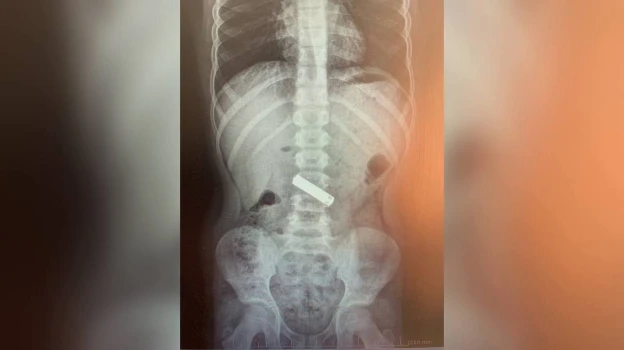

В январе 2025 года в приемное отделение Воронежской областной детской клинической больницы (ВОДКБ) №2 поступили 56 детей с жалобами на возможное проглатывание предметов и еще 12 – с подозрениями на вдыхание инородного тела. Врачи выявили 24 случая нахождения мелких предметов в желудочно-кишечном тракте (ЖКТ) и три случая – в бронхах. Как рассказали в больнице в среду, 4 февраля, под общим обезболиванием медики эндоскопически удалили 15 инородных тел:

• из пищевода – 7 монет и батареек;

• из желудка – 5 магнитов, монет и батареек;

• из бронхов – арахис, фундук и куриную кость.

– Девять выявленных инородных тела специалисты удалили из ЖКТ естественным путем. При этом, из общего числа обратившихся госпитализировали 15 детей. На сегодняшний день всех детей выписали с выздоровлением, – уточнили медики.